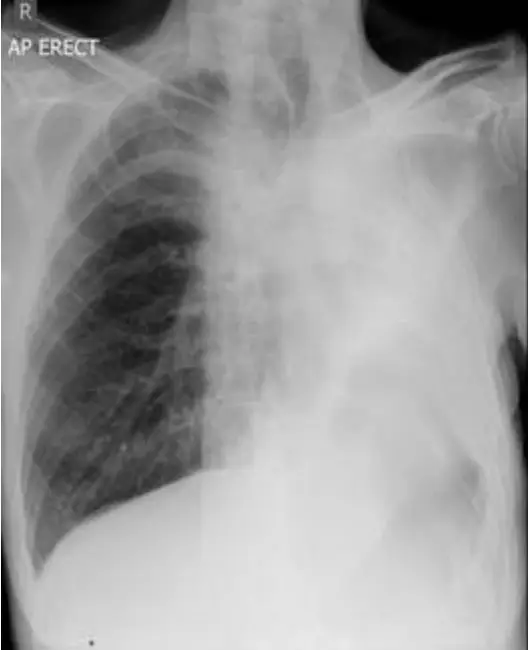

圖(六)(乙病人)

• 同樣左側近全葉不透光,但與圖(五)不同的是氣管及心影輕度向左側(病變同側)移位。

– 向病灶同側移位代表整體胸腔內腔體積減少(negative pressure pull-in),符合大範圍肺組織因中央支氣管阻塞或腫瘤壓迫造成的整葉肺不張(lobar collapse/atelectasis)([pmc.ncbi.nlm.nih.gov](https://pmc.ncbi.nlm.nih.gov/art